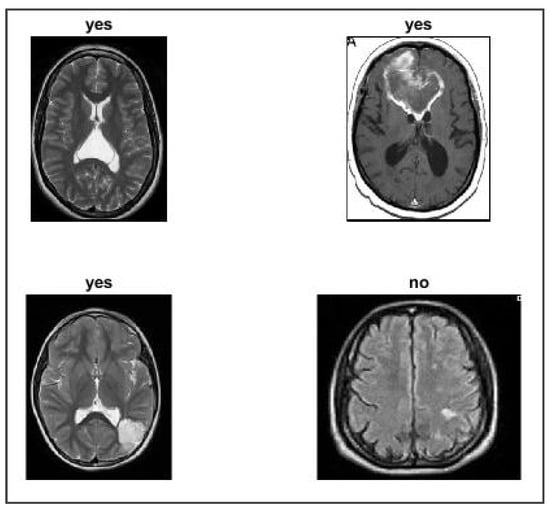

4.1. Dataset